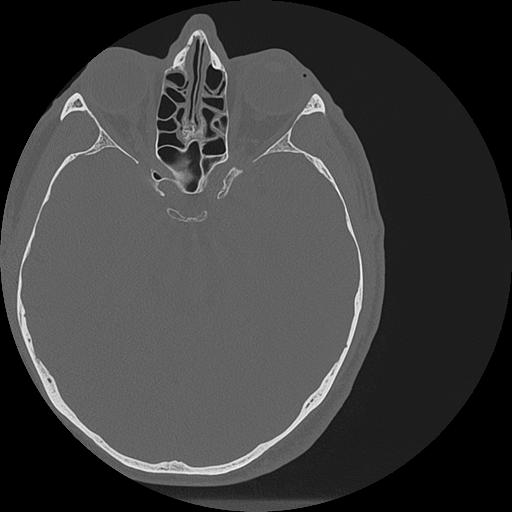

7 HUESO,,Vol,0.5,HUESO,,